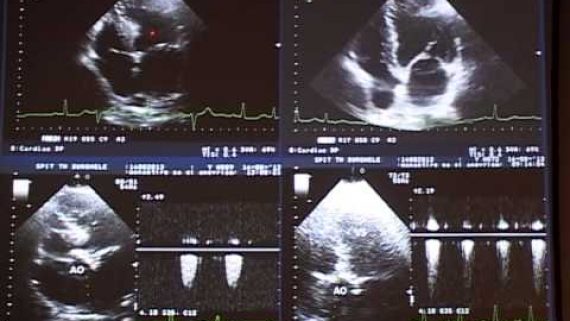

Este o investigaţie noninvazivă ce analizează structura şi funcţia cordului cu ajutorul ultrasunetelor.

Ce reprezinta  o ecocardiografie?

Este principala metodă imagistică în cardiologie şi cea mai solicitată, permitand studierea şi vizualizarea amănunţită a tuturor structurilor cordului (cavităţile, valvele,septurile, muşchii). Datorită acesteia se  pot cunoaşte cu precizie parametrii care definesc atât funcţia de contracţie, cât şi funcţia de relaxare a inimii. Cu ajutorul ei, poate fi măsurată grosimea pereţilor inimii, pot fi vizualizate şi diagnosticate corect leziunile valvulare, congenitale, miocardice. Nu în ultimul rând, ecografia permite şi analizarea pericardului (a învelişului în care se găseşte inima), iar  o inflamaţie la nivelul acestuia poate fi usor depistata in unele cazuri.

Ca investigaţie, este valoroasă atât pentru stabilirea unui diagnostic iniţial, cat si urmarirea, aprecierea severităţii şi ghidarea tratamentului pentru majoritatea afecţiunilor cardiovasculare.

Întrucât utilizează ultrasunetele, ecocardiografia nu prezintă nici un risc pentru pacient, este nedureroasă, neinvazivă şi poate fi efectuată de câte ori aveţi nevoie (lucru pe care nu-l puteţi efectua la o tomografie computerizată, de exemplu). În plus, este recomandată oricărei persoane care are hipertensiune arterială, pentru a cunoaşte în ce măsură îi este afectată inima.Este folosită atât în urgenţele cardiovasculare, cât şi în bolile cronice.

Există mai multe moduri de examinare ecografică: ecografia în mod M, ecografia bidimensională, ecografia Doppler (pulsat, spectral şi color) şi ecografia tridimensională (3D). Toate aceste moduri dau informaţii complementare şi sunt folosite pentru o evaluare cardiacă completă, succesiv sau simultan.